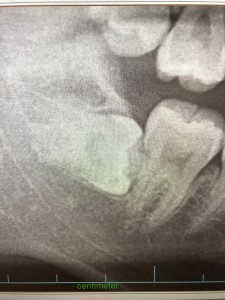

2019年03月08日 水平埋伏智歯 ブログ 下の親知らずに多い横向きになった状態を水平埋伏と呼びますが、抜歯するとなると外科的な侵襲がどうしてもありますので 術後1週間から10日程度顔が腫れます。 また顎のあたりが内出血で青っぽくなる事もあります。 さらに腫れのために、口を大きく開けるのが難しくなりますので食事も思うように最初は取れない事もあります。 後日、糸をとって消毒なども必要です。 神経が近い場合にはしびれなどが残るリスクもありますので十分に相談してから抜歯を行うことをお勧めします。